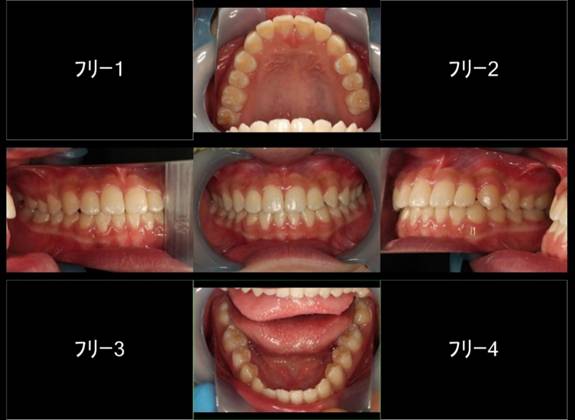

インビザGOによる矯正症例1 16歳男性

|

マウスピース矯正開始前。右上犬歯が内側にありました

前から見たところ

4か月後。犬歯が外側に出てきました

治療終了後10か月